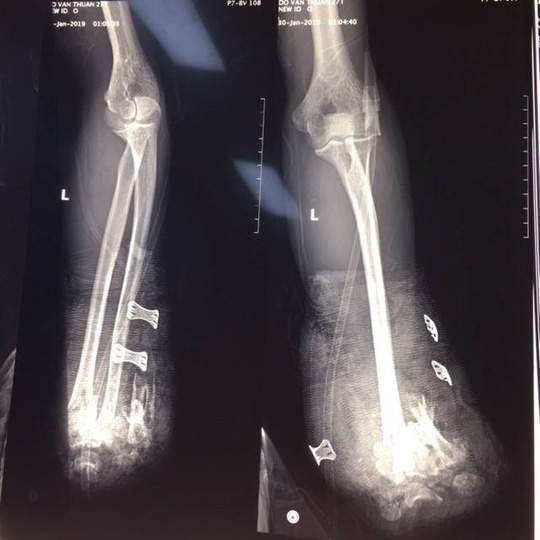

| Hình ảnh X quang cho thấy nạn nhân bị dập nát 1/3 dưới 2 xương cẳng tay - Ảnh: Bệnh viện cung cấp. Ảnh: N. Dung. |

Tại nhiều bệnh viện thời điểm trước và sau Tết Nguyên đán, các cơ sở này ghi nhận nhiều trường hợp nhập viện do pháo tự chế. Cách đây ít ngày, Bệnh viện Trung ương Quân đội 108 đã tiếp nhận bệnh nhân Đỗ Văn T. (25 tuổi, TP Hải Phòng), nhập viện trong tình trạng bị thương nghiêm trọng do pháo nổ. Theo lời kể của người nhà nạn nhân, khoảng 18 giờ ngày 29-1, anh T. đang tự chế pháo nổ tại nhà thì bất ngờ gặp sự cố phát nổ. Sau tiếng nổ lớn, bệnh nhân bị cụt 2 bàn tay, vết thương vùng hàm mặt, chảy nhiều máu, được sơ cứu và chuyển đến Khoa Cấp cứu, Bệnh viện Trung ương Quân đội 108 trong tình trạng: Cụt bàn tay 2 bên, gãy hở xương hàm dưới, chấn thương ngực kín, dập nhu mô thùy trên hai phổi, bỏng rộng vùng ngực, nhiều vết thương nhỏ ở 2 chân.

Tại bệnh viện, bệnh nhân đã được mổ cấp cứu cắt cụt để ngỏ 1/3 giữa cẳng tay phải, cắt lọc cơ dập nát cẳng tay trái, kết xương hàm dưới, sau mổ phải điều trị tiếp tại khoa Hồi sức tích cực của bệnh viện. Hiện tình trạng bệnh nhân đã giữ được tính mạng, tuy nhiên sẽ để lại di chứng nặng nề.